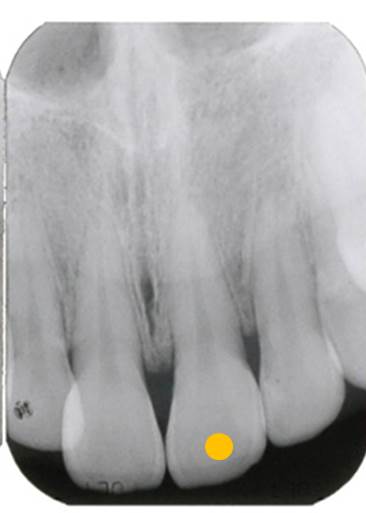

次にレントゲン撮影をします。

このレントゲンで分るのは、神経を取った歯ということです。神経を取った歯は、歯の芯の部分に薬が入っています。よく「歯医者で神経取った」と言われます。歯の中には、神経だけでなく血管が存在します。「神経を取る」というのは、「神経も血管も取る」ということなのです。歯の中の血管を取ってしまえば、白血球が存在しなくなります。神経や血管を取った際に、歯の中に細菌が残ってしまえば後から膿んでくる可能性が非常に高くなるのです。

※参考に、下図の写真は神経や血管を取っていない歯のレントゲン写真です。歯の中に材料が入っていないのが分ります。つまり、神経のある歯は血が通っていて白血球が警備してくれているため、絶対に膿んでくることはないのです。